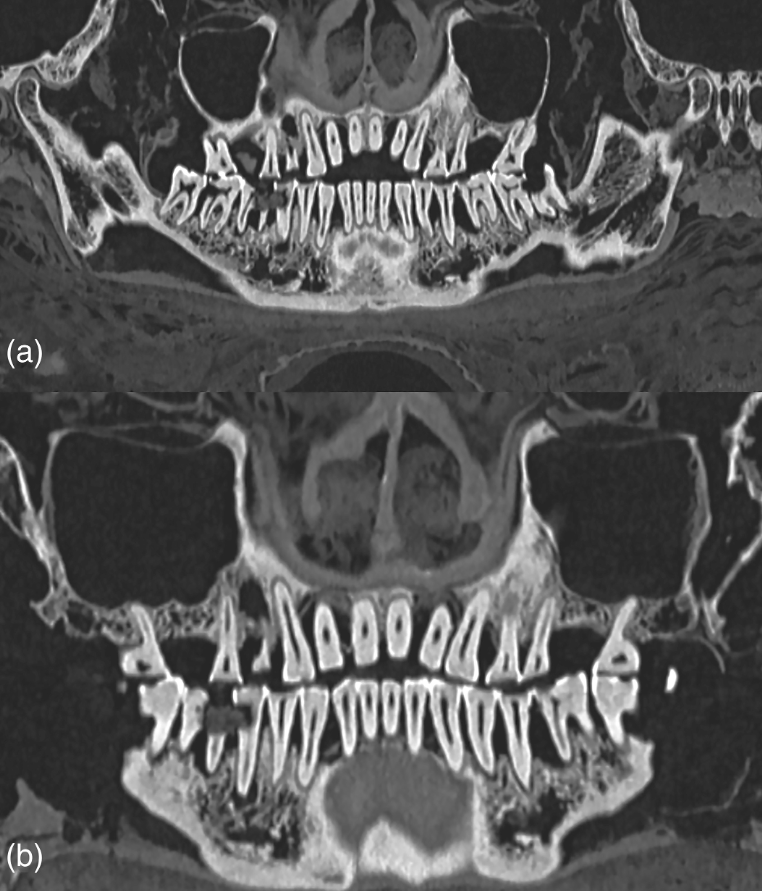

Để có được kết luận này, các chuyên gia đã sử dụng kỹ thuật chụp cắt lớp vi tính (CT) để mô tả đầy đủ về răng xác ướp Ai Cập. Ảnh: @Bảo tàng Khảo cổ học Quốc gia Athens.

Các nhà nghiên cứu đã tìm thấy một khoang xốp trong răng của xác ướp này chứa đầy vật liệu trám bảo vệ. Ảnh: @Bảo tàng Khảo cổ học Quốc gia Athens.

Tất nhiên, việc trám răng như vậy được thực hiện như một hình thức trị liệu chứ không phải là một phần của quá trình ướp xác. Ảnh: @Bảo tàng Khảo cổ học Quốc gia Athens.

Ngoài ra, các nhà khảo cổ học cũng tìm thấy bằng chứng về tình trạng nhiễm trùng nướu nghiêm trọng trên xác ướp này. Nghiên cứu không tập trung vào nguyên nhân cái chết của xác ướp, nhưng đặc điểm của hộp sọ cho thấy nó thuộc về một người đàn ông trưởng thành, qua đời ở độ tuổi đôi mươi. Ảnh: @Bảo tàng Khảo cổ học Quốc gia Athens.